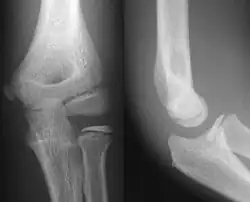

- Elbow - AP and Lateral. Radial head projections available on request

-

Lateral projection -

Anteroposterior projection -

Left elbow by 30 degrees internal oblique projection -

Left elbow by 30 degrees external oblique projection